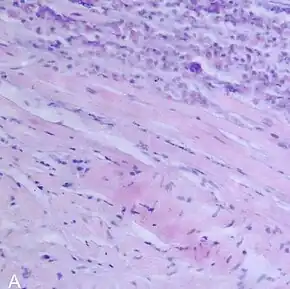

| A microscope image of myocarditis at autopsy in a person with acute onset of heart failure | |

Most forms of myocarditis involve the infiltration of heart tissues by one or two types of pro-inflammatory blood cells, lymphocytes and macrophages plus two respective descendants of these cells, NK cells and macrophages. Eosinophilic myocarditis is a subtype of myocarditis in which cardiac tissue is infiltrated by another type of pro-inflammatory blood cell, the eosinophil. Eosinophilic myocarditis is further distinguished from non-eosinophilic myocarditis by having a different set of causes and recommended treatments.[34][18]

The gold standard is the biopsy of the myocardium, in general done in the setting of angiography. A small tissue sample of the endocardium and myocardium is taken and investigated. The cause of the myocarditis can be only identified by a biopsy. Endomyocardial biopsy samples are assessed for histopathology (how the tissue looks like under the microscope): myocardial interstitium may show abundant edema and inflammatory infiltrate, rich in lymphocytes and macrophages. Focal destruction of myocytes explains the myocardial pump failure.[10] In addition samples may be assessed with immunohistochemistry to determine which types of immune cells are involved in the reaction and how they are distributed. Furthermore, PCR and/or RT-PCR may be performed to identify particular viruses. Finally, further diagnostic methods like microRNA assays and gene-expression profile may be performed.